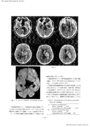

基底核部高血圧性脳出血劇症型の検討